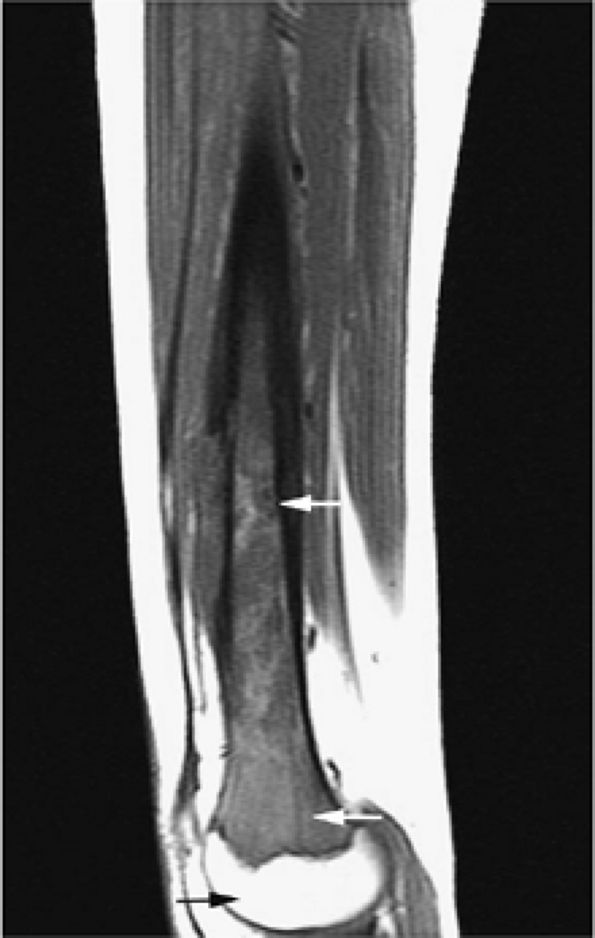

FIGURE 13.74 ● Gaucher disease involving the appendicular skeleton. Low-signal marrow infiltration is noted on a coronal image of the femurs (A) and lower legs (B). Extension into the epiphysis and distal skeleton is characteristic of advanced disease.

|